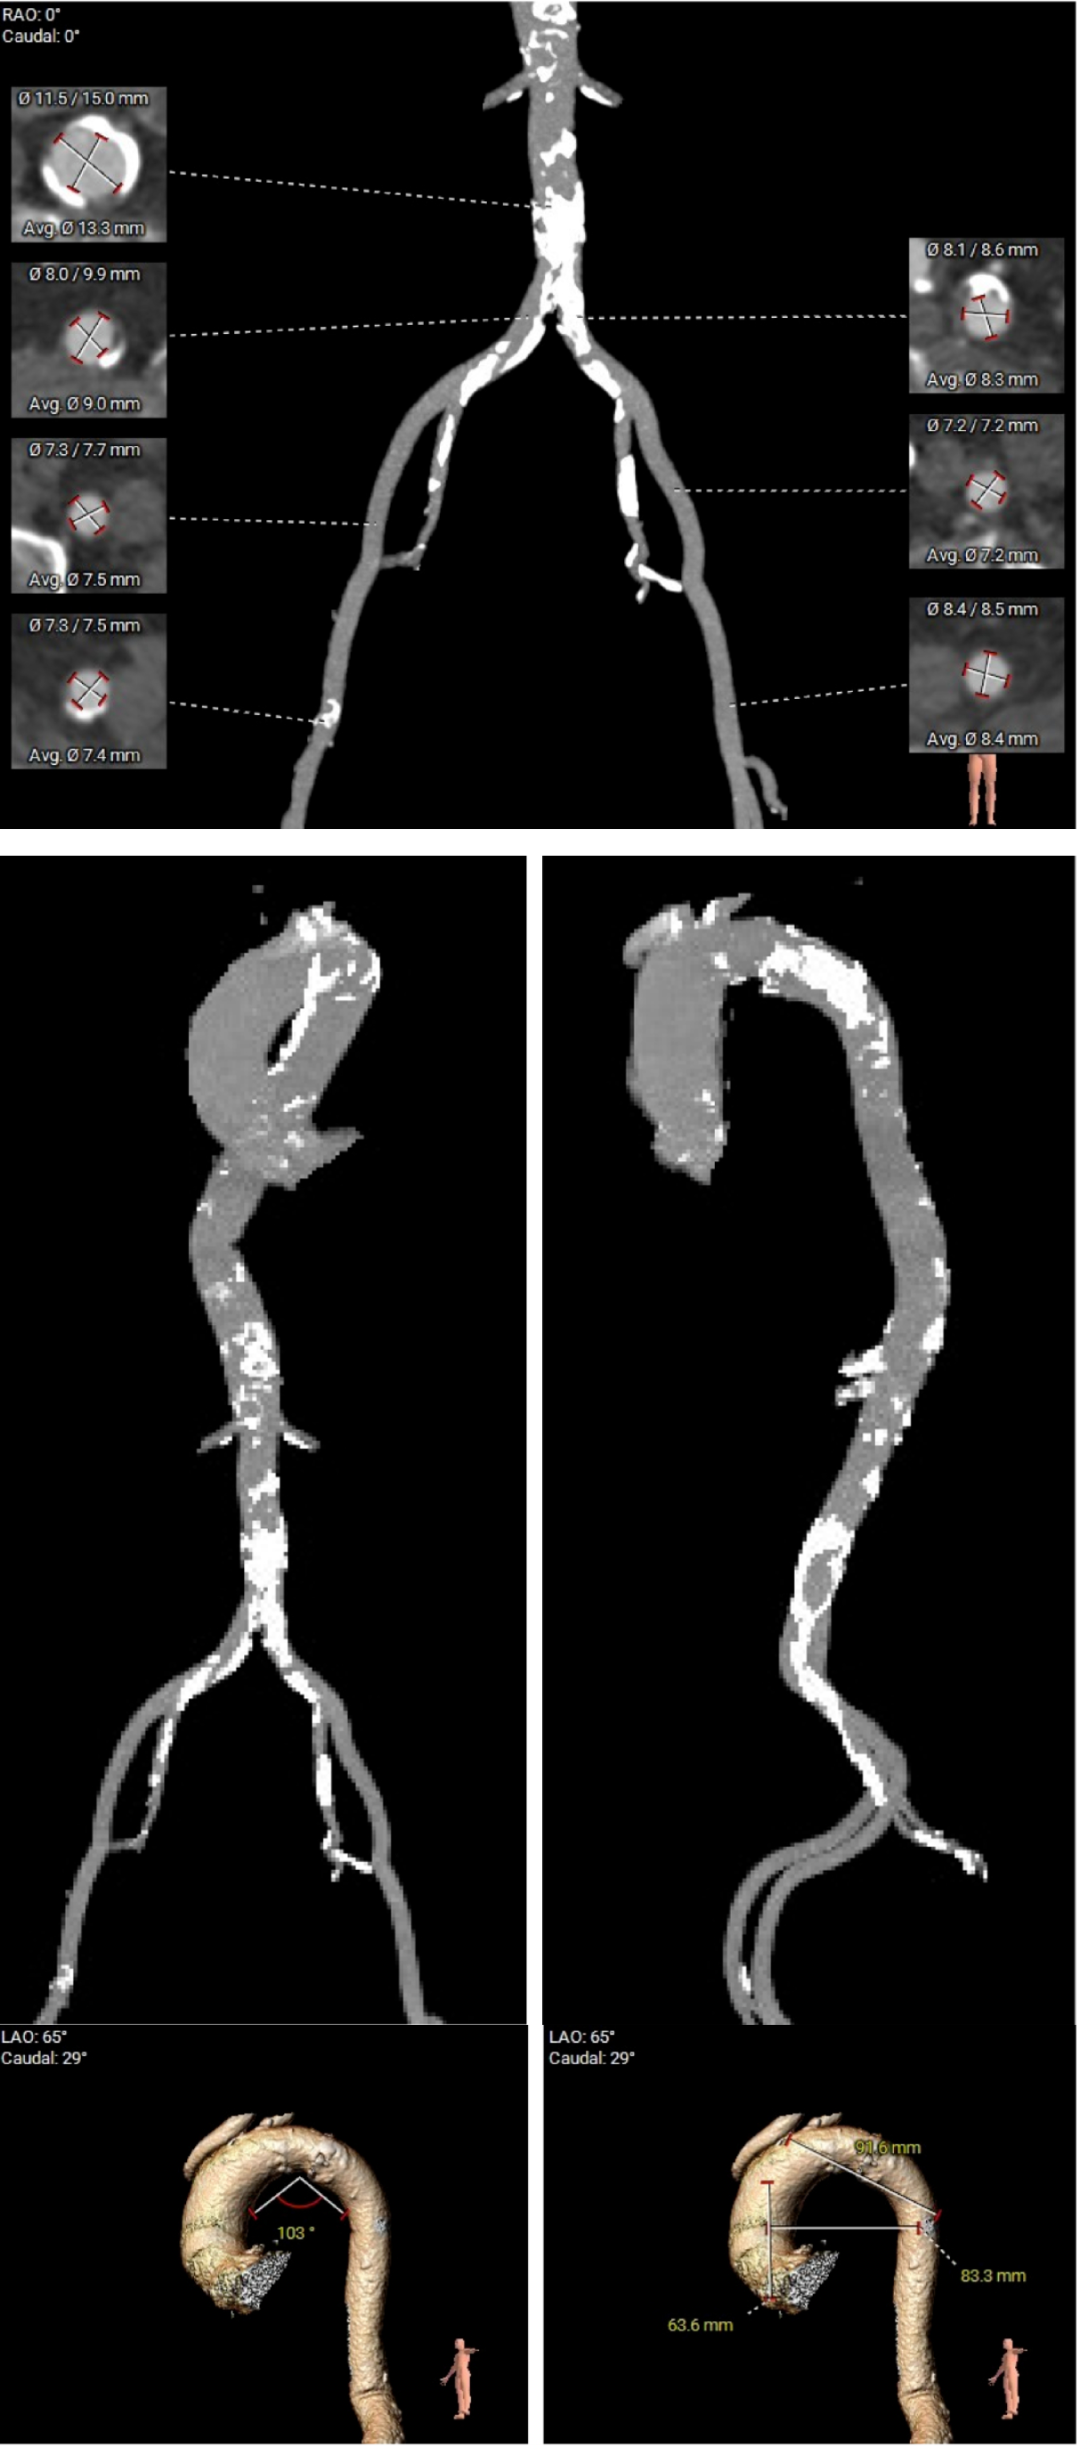

术前CT评估显示,患者瓣膜解剖条件总体具备经导管治疗基础,双侧冠脉阻塞风险偏低。

但与此同时,CT也提示患者存在冠状动脉三支严重钙化病变。也就是说,除了主动脉瓣问题外,供应心脏本身的血管也已经出现明显病变。如果不先处理冠脉问题,后续瓣膜治疗中的风险会进一步上升。

▲瓣膜评估

▲冠脉评估

▲入路评估

进一步评估显示,患者瓣膜狭窄程度重,瓣叶钙化明显,左心室腔径偏小,手术中对器械通过、瓣膜释放以及循环稳定性的要求都更高。团队结合术前影像和整体身体状况,制定了周密的介入治疗方案,并做好相关风险预案。

CT评估

瓣膜评估